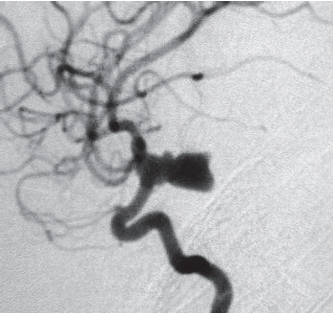

第一次手术前右颈内动脉的侧视图血管造影,显示一个向后突出的巨大囊状动脉瘤。